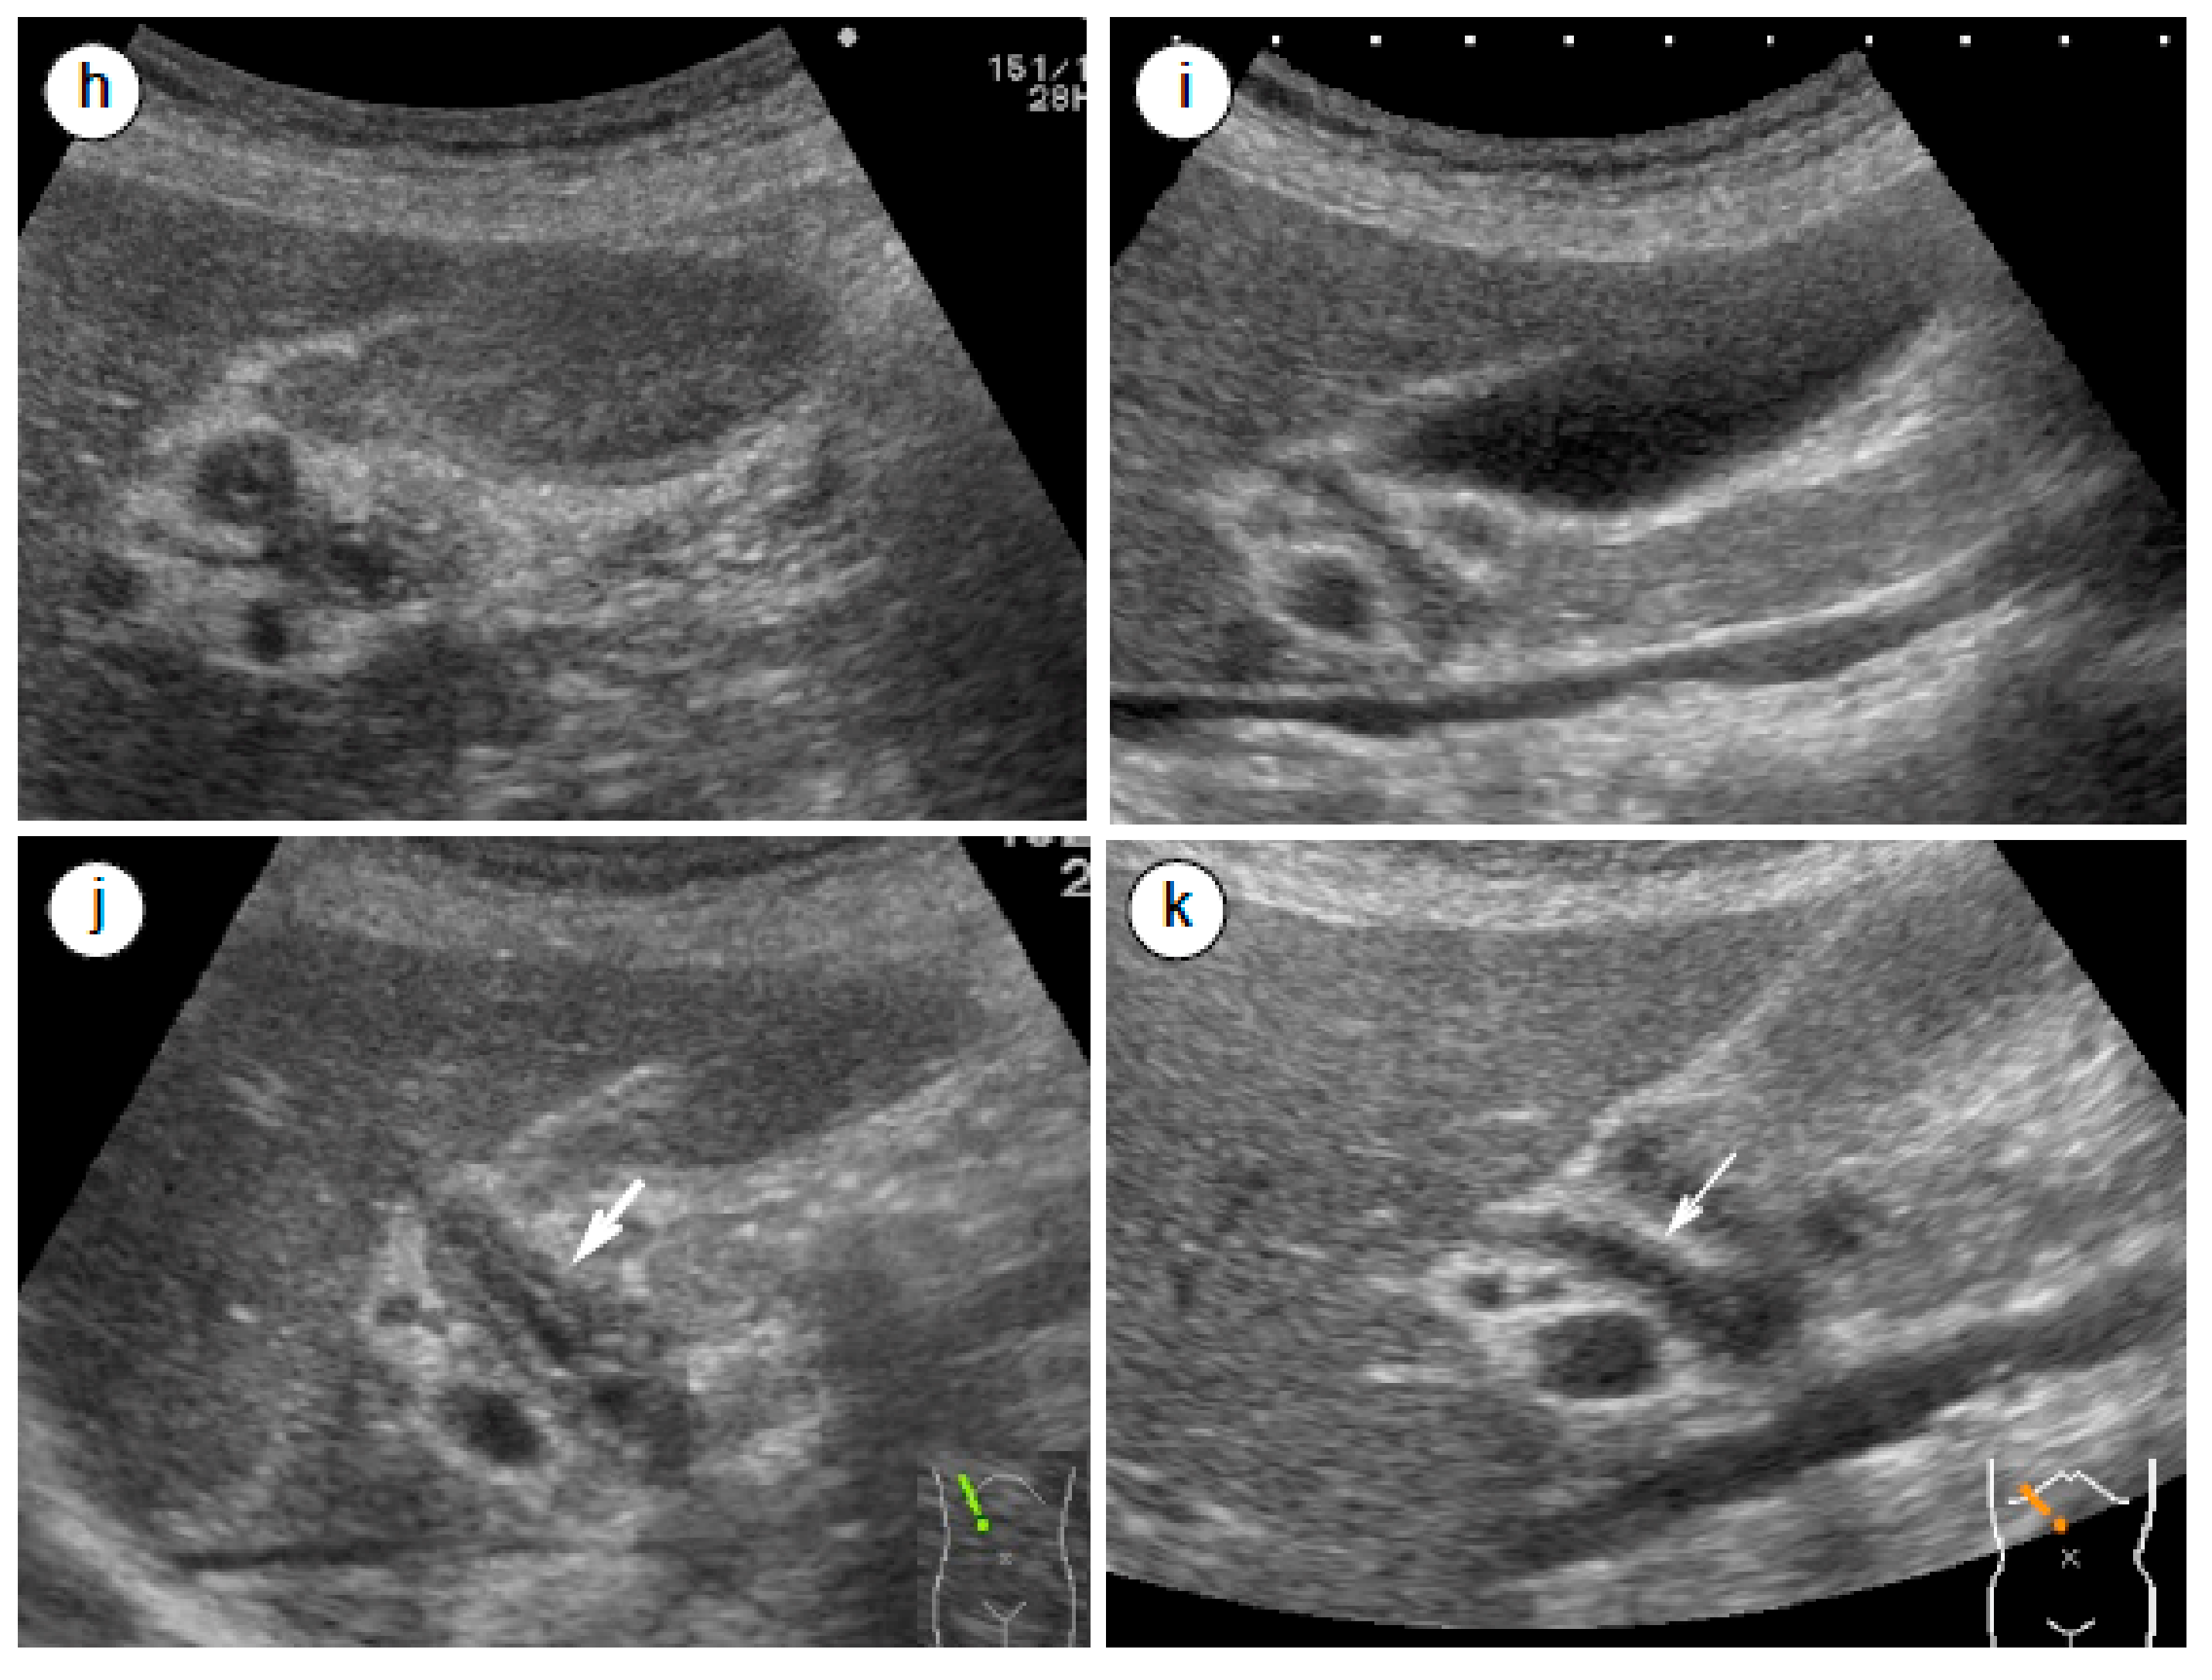

4.3. Radiological and Ultrasonographic Evaluation for Assessing AIP Response to Steroids

- Matsubayashi, H.; Yoneyama, M.; Nanri, K.; Sugimoto, S.; Shinjo, K.; Kakushima, N.; Tanaka, M.; Ito, S.; Takao, M.; Ono, H. Determination of steroid response by abdominal ultrasound in cases with autoimmune pancreatitis. Dig. Liver Dis. 2013, 45, 1034–1040. [Google Scholar] [CrossRef]

- Matsubayashi, H.; Furukawa, H.; Maeda, A.; Matsunaga, K.; Kanemoto, H.; Uesaka, K.; Fukutomi, A.; Ono, H. Usefulness of Positron Emission Tomography in the Evaluation of Distribution and Activity of Systemic Lesions Associated with Autoimmune Pancreatitis. Pancreatology 2009, 9, 694–699. [Google Scholar] [CrossRef]

- Shigekawa, M.; Yamao, K.; Sawaki, A.; Hara, K.; Takagi, T.; Bhatia, V.; Nishio, M.; Tamaki, T.; El-Amin, H.; Sayed, Z.-A.; et al. Is (18)F-fluorodeoxyglucose positron emission tomography meaningful for estimating the efficacy of corticosteroid therapy in patients with autoimmune pancreatitis? J. Hepatobiliary Pancreat. Sci. 2010, 17, 269–274. [Google Scholar] [CrossRef]